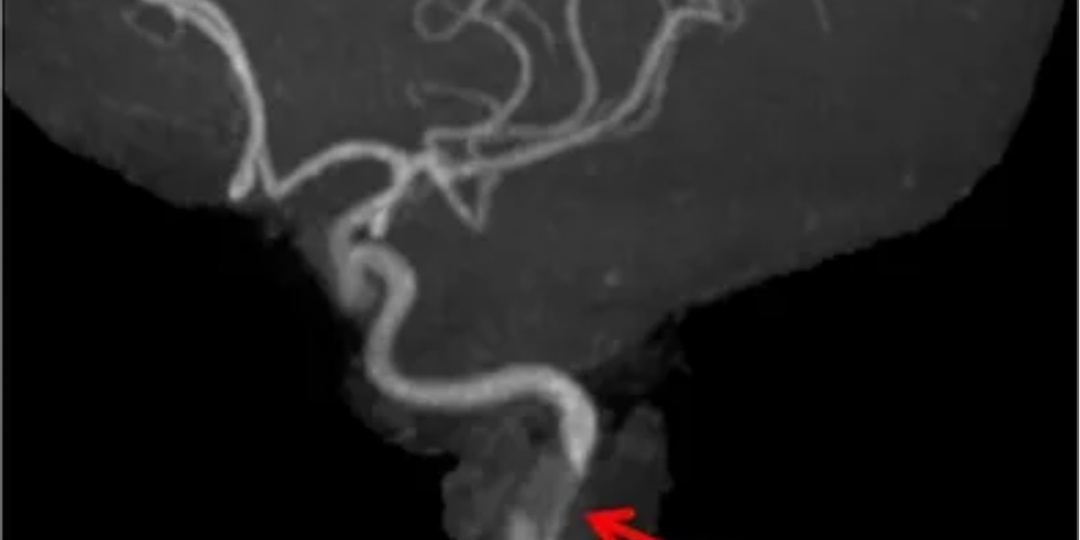

Часто головокружение кажется простым симптомом: переутомление, давление, остеохондроз. О чем ещё думают часто? Сосуды, вестибулярный аппарат? Но порой за ним скрываются истории, которые не укладываются в медицинские учебники. Они напоминают, что человек- это не только набор органов и диагнозов, но и сложный мир, где переплетаются здоровье, психология и социальные обстоятельства. Эта история началась с обычного вызова. На пороге встретила встревоженная женщина лет пятидесяти: "Доктор, мама совсем не в себе. Забывает всё, говорит странности, будто к ней кто-то приходит… И она его… любит". В голосе дочери — смесь страха и стыда. "Вы знаете, она интеллигентнейший человек, преподаватель литературы и русского языка. А теперь ведёт себя как подросток: дурашливо, вызывающе, хихикает без причины". Войдя в комнату, я увидел пожилую женщину (назовем её Галина В.) с аккуратной седой причёской. Она сидела в кресле, игриво поправляла халат. "О, наконец-то мужчина в доме!"- сказала она с улыбко